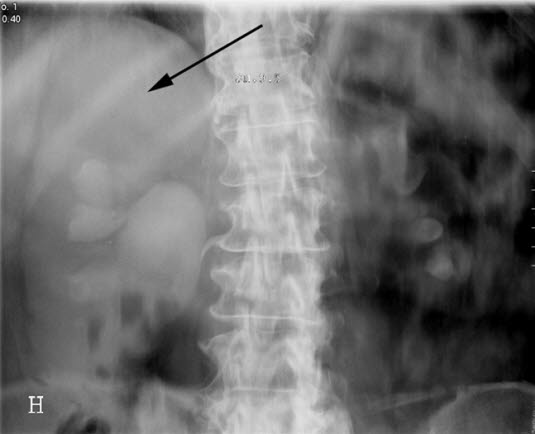

Urografi

Rund oppfylling i øvre pol av høyre nyre (pil).

Øvre calyxgruppe er forskjøvet nedover.

For å utelukke tumor må det gjøres ultralyd.